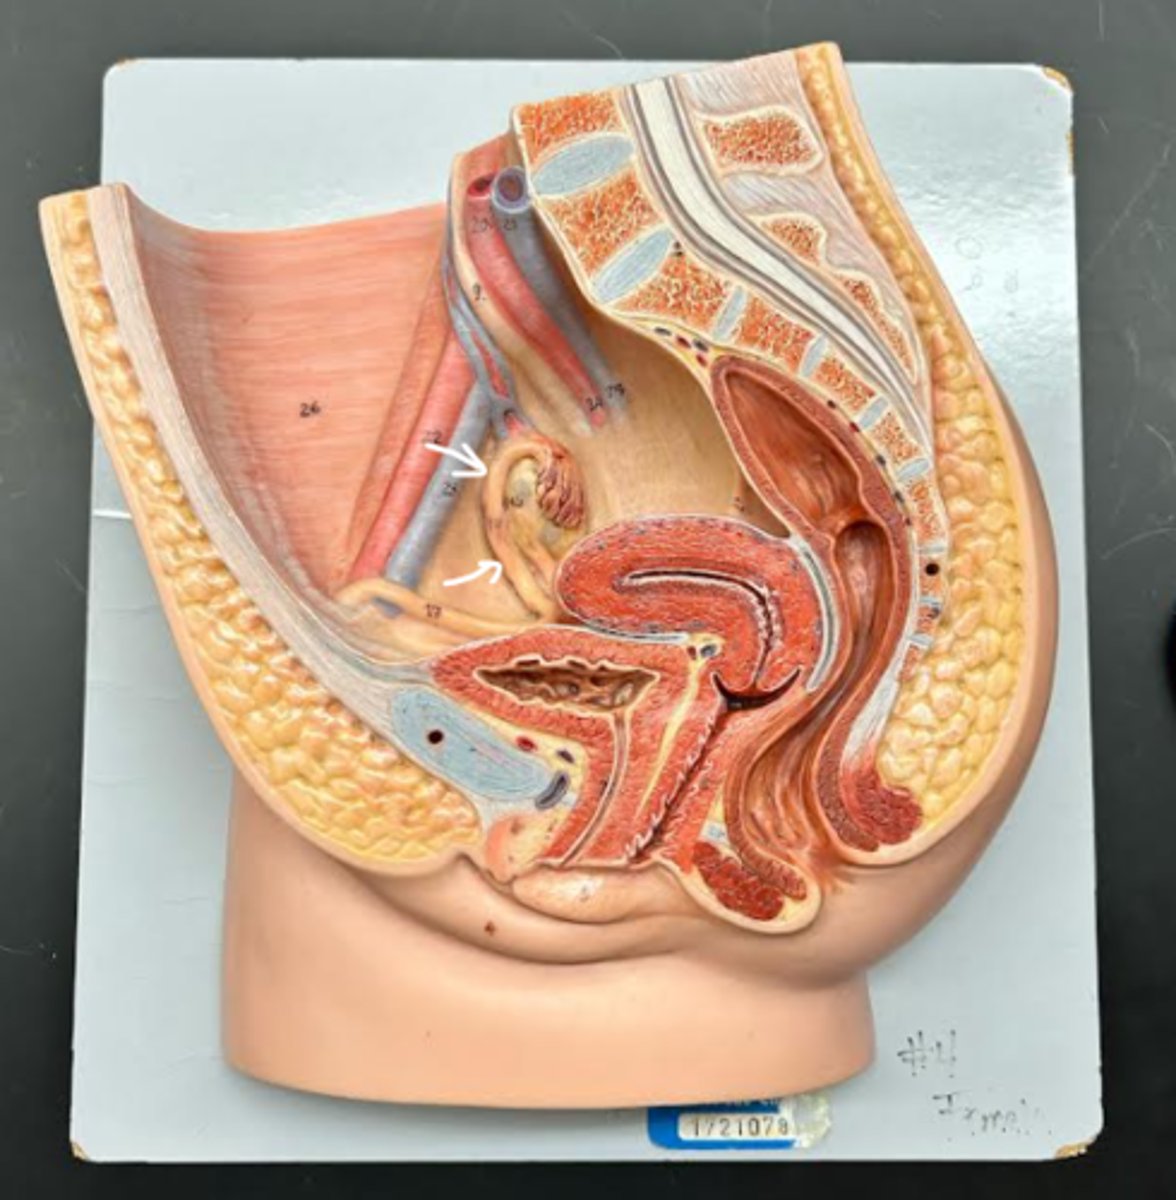

Chapter 29 Anat Phys: Female Reproductive System

Vagina

Vaginal orifice

Hymen

Vaginal fornix

Ovary

Fallopian tube

Fimbriae

Infundibulum

Ampulla

Isthmus

Uterus

Perimetrium

Myometrium

Endometrium

Fundus

Body of uterus

Cervix

Internal os

Cervical canal

External os

Labia majora

Labia minora

Prepuce

Vestibule

Clitoris

External urethral orifice